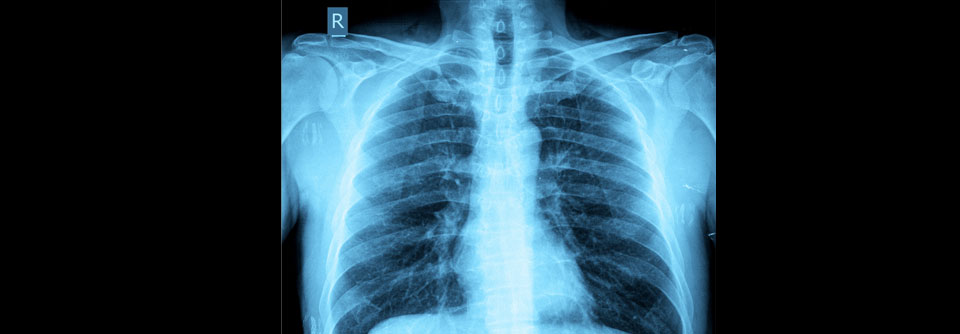

Seltene Erreger und Pneumonie

Von CMV-Infektion bis Vogelgrippe

Hantaviren der neuen Welt, Nipah-Virus, H5N1 und weitere Vogelgrippeviren: In sehr seltenen Fällen verursachen diese Erreger auch bei immunkompetenten…